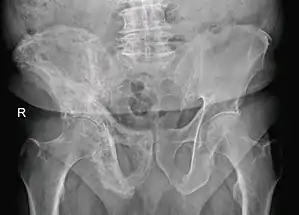

![]() Хвороба Педжета правої кістки стегна у 80-річного чоловіка. Хвороба Педжета правої кістки стегна у 80-річного чоловіка. | |

Основним інструментальним методом діагностики є рентгенографія. Типовими рентгенологічними ознаками є остеосклероз, що чергується ділянками остеолізу, збільшення кістки й деформація. Можливе проведення сцинтиграфії кісток, яка дозволить визначити поширеність захворювання і виявити можливі асимптотні ураження кісток. При можливому метастатичному ураженні кісток слід проводити кісткову біопсію.